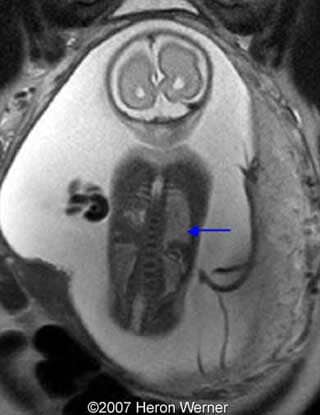

Figures 8, 9: Axial view on T2-weighted shows the heart placed to the right side and the stomach in the same place (red arrow). In the figure 10 we can see the normal kidneys (arrows).

9

Figures 10, 11, 12: Sagittal T2-weighted shows the liver-up (blue arrow) and the stomach in the chest (red arrow).